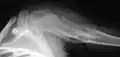

| X-ray image showing enchondromas localized in the lower part of the radius of a 7-year-old girl with Ollier disease. | |